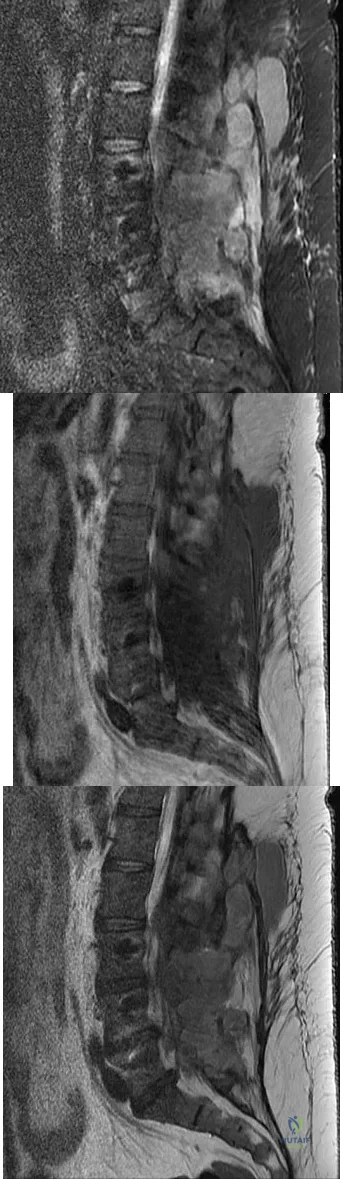

A 44-year-old woman has had lower extremity dysesthesias, urinary incontinence, and has been unable to walk for the past 2 days. She reports no pain or history of trauma. She notes that 3 weeks ago she missed work for 2 days because of back pain, but it resolved with rest. Examination shows decreased or absent sensation below the knees, no motor function below the knees, and decreased rectal tone. Catheterization results in a postvoid residual of 2,000 mL. Plain radiographs and MRI scans without contrast are shown in Figures 1a through 1d. What is the next most appropriate step in management?

The patient has had a clear and sudden onset of a profound neurologic deficit. The radiographic studies suggest a lesion in the conus medullaris that appears to be intradural and intramedullary. MRI, with and without contrast, will best evaluate this mass further. The addition of gadolinium allows further evaluation of vascularity and the extent of the lesion. Eichler ME, Dacey RG: Intramedullary spinal cord tumors, in Bridwell KH, Dewald RL (eds): The Textbook of Spine Surgery, ed 2. Philadelphia, PA, Lippincott-Raven, 1997, vol 2, pp 2089-2116.

Beaty JH (ed): Orthopaedic Knowledge Update 6. Rosemont, IL, American Academy of Orthopaedic Surgeons, 1999, pp 81-87.